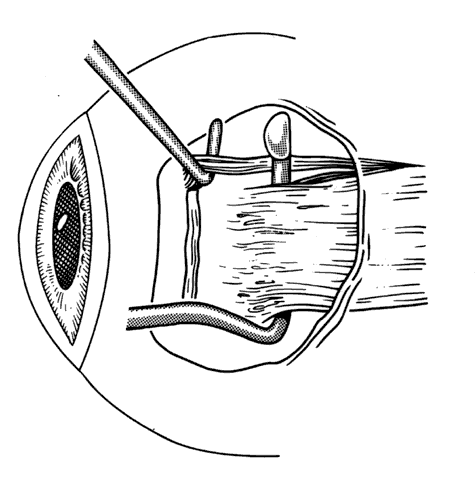

After the incision has been made and the dissection through Tenon's capsule has been completed to the surface of the sclera, muscle hooks are passed behind the rectus muscle to identify the insertion of the muscle. Once the muscle has been “hooked,” there is improved control of the globe. This will facilitate the blunt and sharp dissection that will be needed to reflect the conjunctiva over the tendon of the muscle (Fig. 15). Sharp dissection beneath the conjunctiva is used to separate fibrous tissue and restrictive bands from the surface of the muscle capsule and the sclera (Figs. 16 and 17). Frequently it will be necessary to remove small amounts of tissue to visualize the area of contact of the muscle insertion (Fig. 18).

Fig. 15. A Jameson muscle hook is under the insertion of a previously recessed horizontal rectus muscle. The insertion is cleared of any residual adhesive bands and scar tissue.